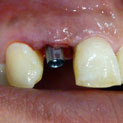

En estos casos han sido tratados con la filosofía de all-at-once, en la

misma sesión: